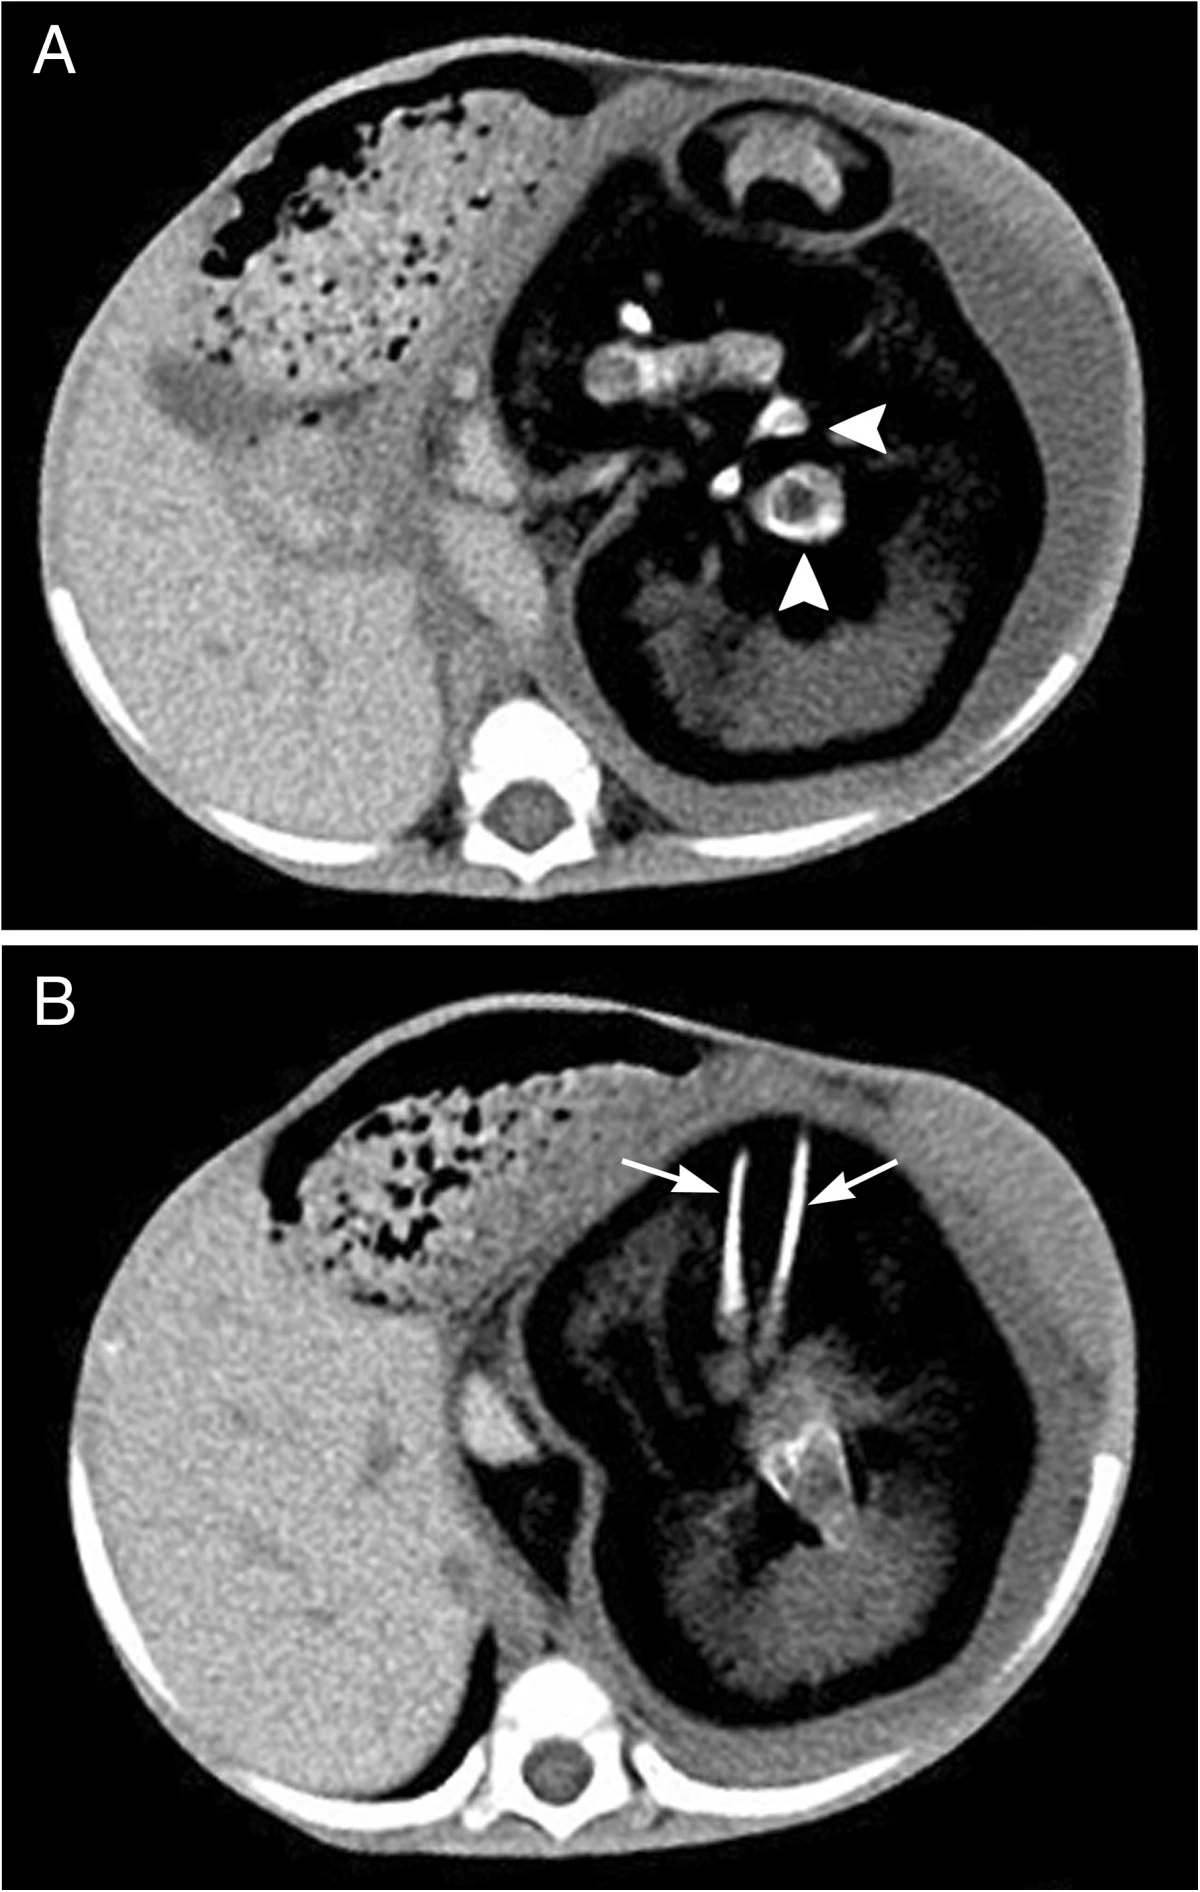

НемедицинаFigure 1. На компьютерной томографии брюшной полости видно образование с кальцинированными и липоматозными компонентами внутри. A. Хорошо сформированное тело позвонка (указано стрелкой); B. Стрелка указывает на длинные затемнения, соответствующие конечностям плода.